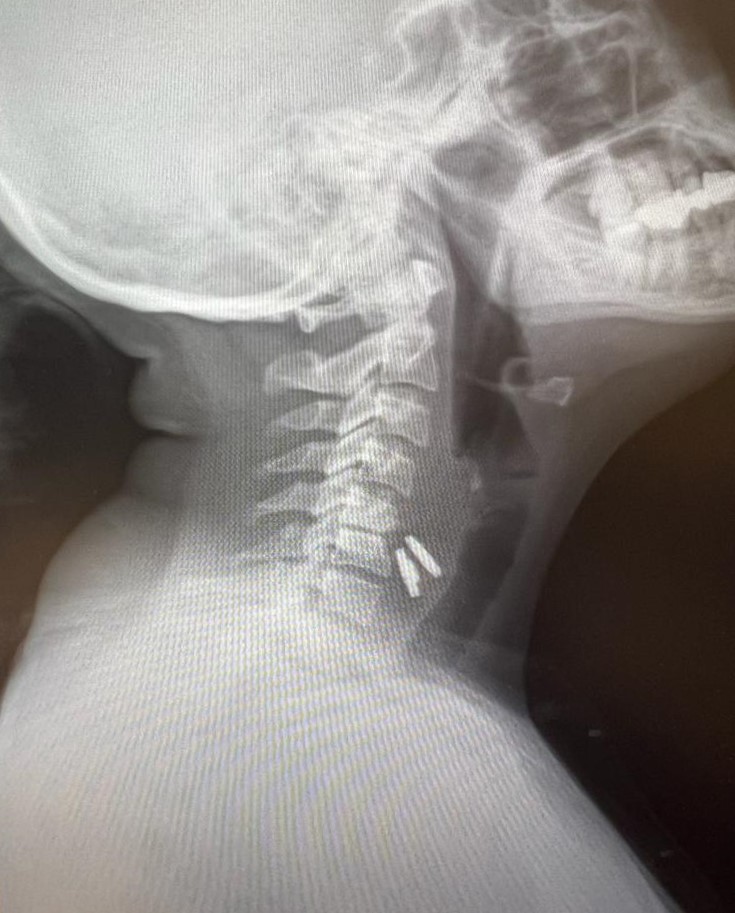

Kahramanmaraşlı ev hanımı Sultan Tıraş (40), sekiz ay önce kolunun sık sık uyuşması nedeniyle bir sağlık kuruluşuna başvurduğunda, boyun fıtığıteşhisi konulduğunu ve yapılan ameliyatta boyun omurlarına metal diskyerleştirildiğini söyledi.

Bursa’daki doktorun, boyun omuruna takılan metal diskin gırtlağını delme ihtimali olduğunu bildirdiğini kaydeden Tıraş, Kahramanmaraş’a döndüğünde doktorların acil ameliyat olması gerektiğini söylediklerini ifade etti.

Tıraş, Gaziantep’te bir özel hastanede kendisini muayene eden doktorun, ameliyatla takılan boyundaki diski ameliyatla aldığını, ancak diğerinin yemek borusunu delip mideye indiğini ve ciddi sorunla karşı karşıya olduğuna dikkat çekerek, acilen bu konuda deneyimli olan SANKO Üniversitesi Hastanesi’nde Prof. Dr. Levent Elbeyli’ye yönlendirdiğine vurgu yaptı.

Sultan Tıraş’ın Gaziantep’te başka özel hastanede yapılan radyolojik tetkikler ve değerlendirmeler sonucu daha önce başka bir merkezde boyun omurlarına yerleştirilen metal disklerin yerinden oynadığının saptandığını anımsatanProf. Dr. Elbeyli, sözlerini şöyle sürdürdü:

“O hastanede beyin ve sinir cerrahisi uzmanı tarafından ameliyata alınan Sultan Tıraş’ın boyun omuruna konulan iki aparattan biri çıkarılmış, ancak diğerinin yemek borusunu delip mideye indiğibelirlenmiş.İlgili hekim bana ulaşarak bilgilendirmeyi yaptı ve hastayı hastanemize sevk etti.

Yemek borusunda oluşan delik ve delikten mideye inen metalik cerrahi aparat görüldü. Göğüs kafesi içinde ciddi bir iltihap ve hava birikimi vardı. Hasta yakınları durum ile ilgili bilgilendirildi, riskler kendileri ile paylaşılarak hastamıza tıbbi müdahale edebilmemiz gerekli onayları alındı.”